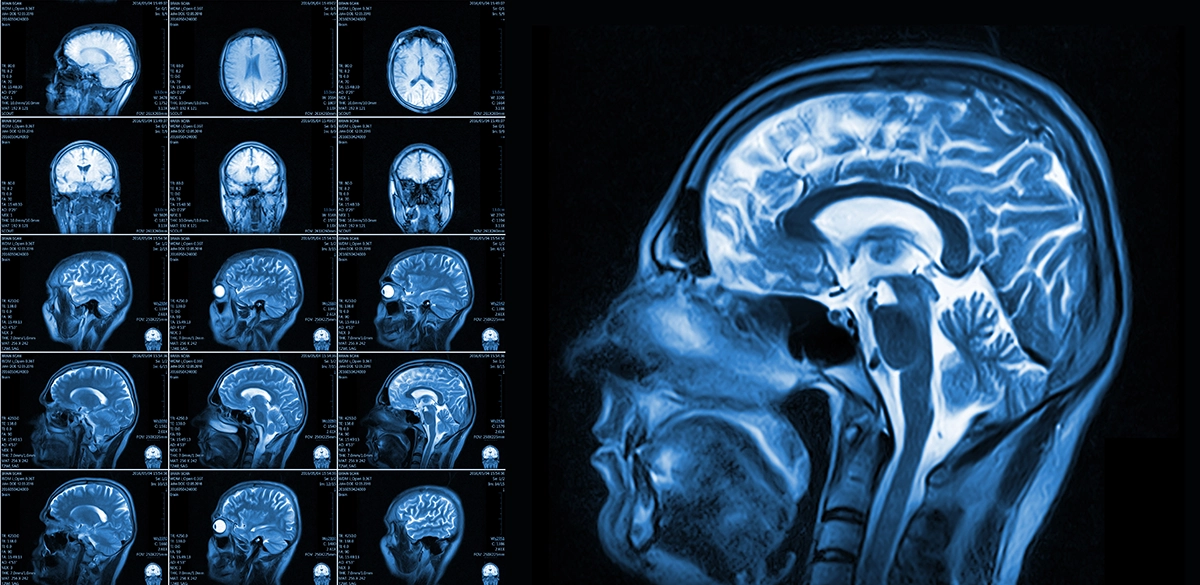

3 types of brain scans

EEG, MRI, PET scan

what does MRI scan record

how does it do this

body and brain tissue, uses magnetic fields and special radio receivers